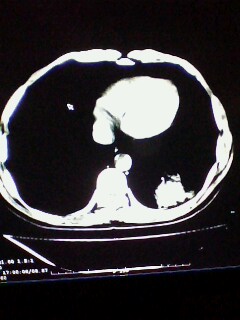

标题: CT28315:咳嗽咳痰咯血半月并胸痛 [打印本页]

1、纵膈窗效果不好,初步考虑左肺下叶感染性病灶,建议正规抗炎治疗后复查   2、右肺下叶陈旧性病灶伴局部胸膜增厚。

考虑左肺下叶周围型肺癌.图象欠清,请问病人贵更?

左下肺肿块影,深分叶,考虑肺癌。

左下肺球形病灶,考虑:1:球形肺炎;2:周围型肺癌不除外,建议治疗后复查

不排除左肺下叶周围型肺癌可能!建议穿刺活检!

考虑左肺下叶周围型肺癌并阻塞性肺炎。